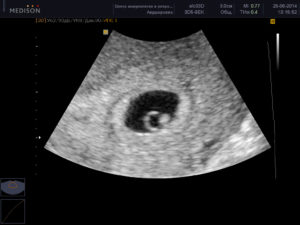

При визуализации матки без увеличения пятинедельная беременность видна на экране в виде округлого или овального пузырька. Однако общая картина уже отличается от той, что специалист мог наблюдать, например, на 3 неделе. Меняется не только размер плодного яйца, но и его содержимое: внутри при увеличении изображения в несколько раз можно разглядеть желточный мешок и сам эмбрион.

На УЗИ в 5 недель беременности, увидеть будущего ребенка сложно, скорее это похоже на головастика, находящегося в оболочке с жидкостью. Это так называемое плодное яйцо с внезародышевыми структурами. К ним относят хорион, амнион и желточный мешочек. Во время ультразвукового исследования врач определяет диаметр плодного яйца, который в норме на данном сроке составляет около 4 мм.

На этом сроке размер эмбриона значительно увеличился и теперь его размер составляет около 10 мм. С каждым днем он будет все активнее и активнее расти, приобретая привычный человеческое обличье. Сейчас эмбрион выглядит, как С-образное образование.

Но присмотревшись можно уже отличить, где будет голова, а где появятся конечности. Сделанное фото-УЗИ на 4-5 неделе беременности для родителей не будет настолько информативным, как для врача.

Но для родителей это отличная возможность сохранить в фотоальбоме момент первого знакомства с их малышом. И пусть на фото будет видна лишь маленькая горошинка на черном фоне, окруженном тонкой белой линией, зато это самое дорогое, чего ожидает каждая женщина.Ультразвуковая фотография на данном сроке – это возможность подтверждения, оценки и предупреждения патологий в жизни растущего эмбриона.

Фото УЗИ на данном сроке может быть размытым, а сам эмбрион на нем напоминать формой креветку или маленький цилиндрик. Если снимок и аппарат качественные, то можно будет увидеть хвостик эмбриона и его головку, а также зачатки ручек и ножек, а иногда даже ротовой и носовой щелей, глазок, пальцев и ушных раковин. Что же касается матки, то она своей формой должна напоминать яйцо.